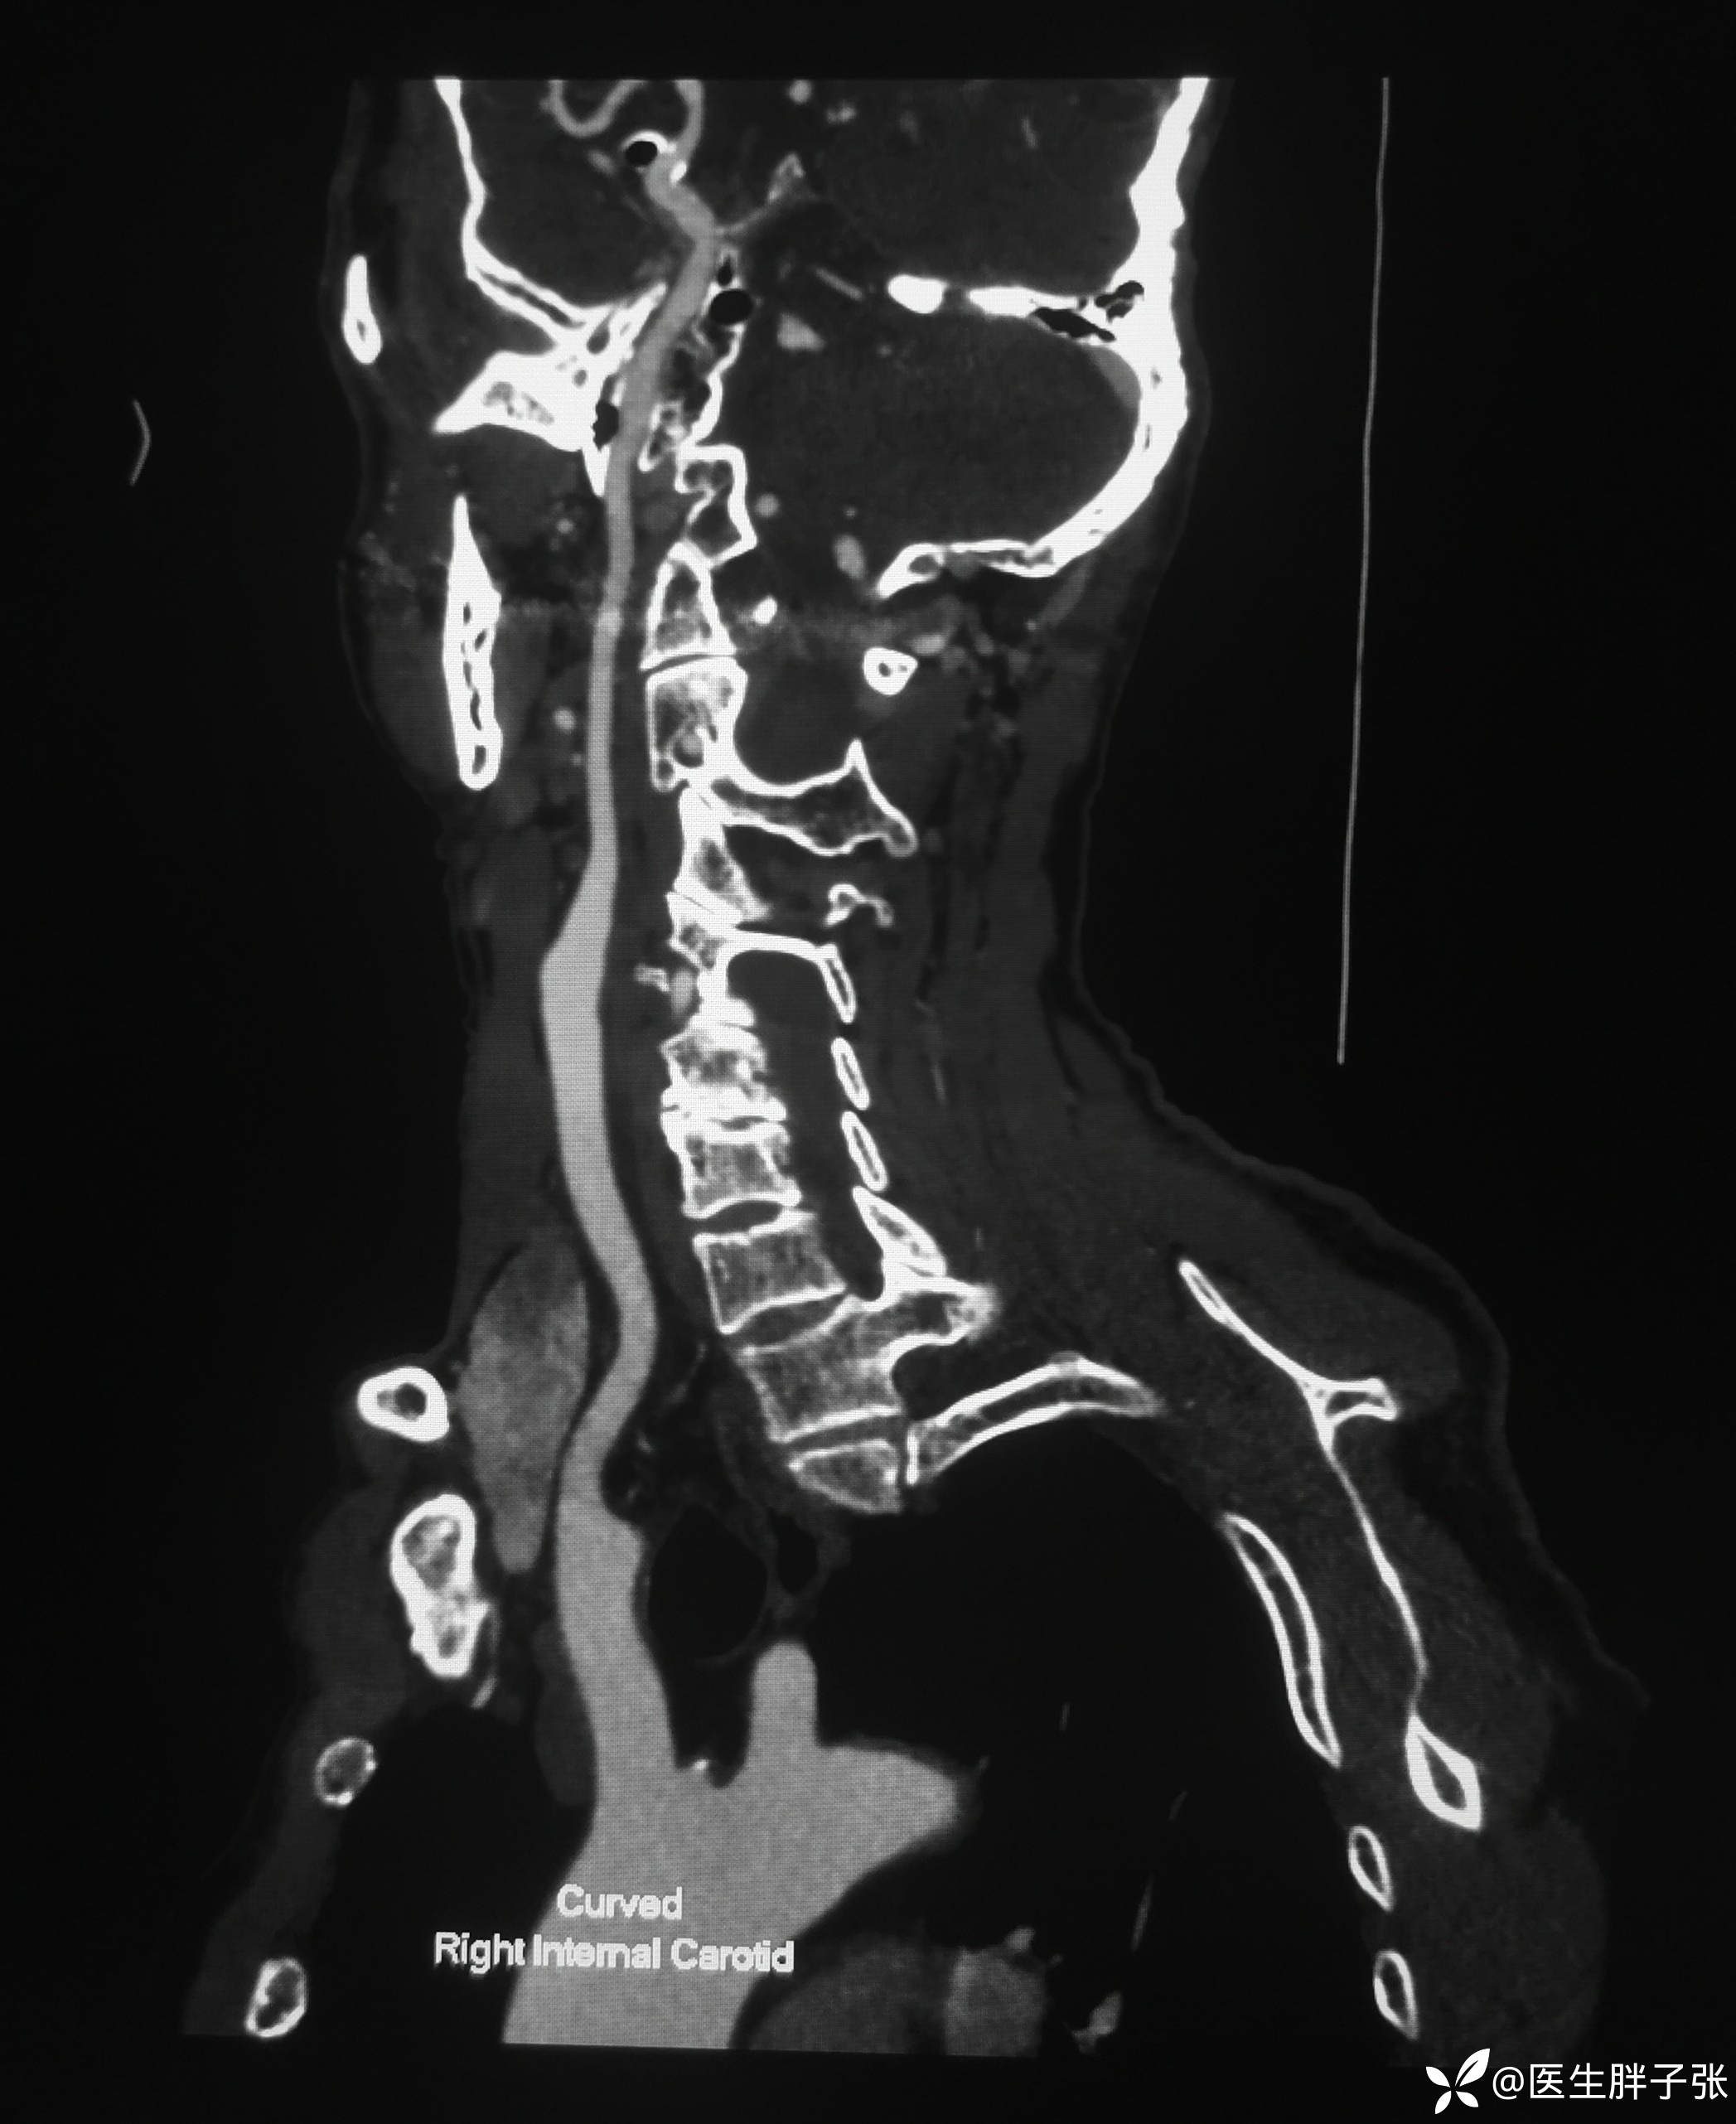

头颈部CTA